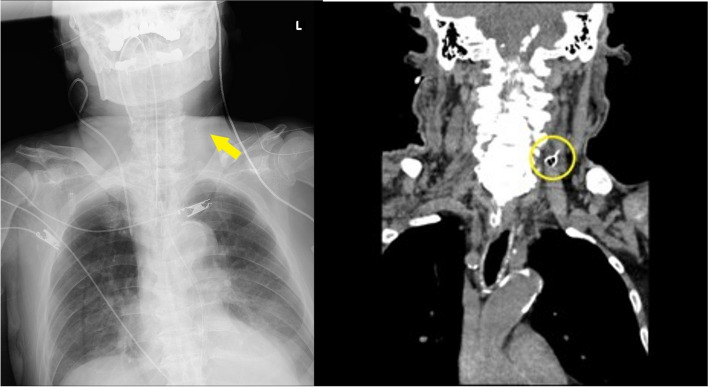

Background: The standard of care for placement of a central venous catheter (CVC) includes a real-time ultrasound (US)-guided technique. We describe a rare case in which the guidewire penetrated the posterior wall of the vessel, forming a knot, which precluded simple removal. This occurred despite the procedure being performed under real-time US guidance. The guidewire was eventually removed under fluoroscopic guidance in a hybrid operation room.

Case presentation: An 89-year-old male underwent the placement of a CVC in the left internal jugular vein. During the US-guided procedure, the guidewire penetrated the posterior wall of the vessel and formed a knot, which impeded simple removal. This was confirmed by radiologic imaging. Using a short sheath and a push-pull technique, the radiologist was able to untangle the knot to allow for catheter removal. The guidewire was safely removed without vascular injury.

Conclusions: A very rare complication of guidewire knotting was observed despite the use of US-guidance during needle and wire placement. The use of US, computed tomography, and fluoroscopy were beneficial for diagnosis, while the hybrid operating room provided the optimal environment for the removal procedure.